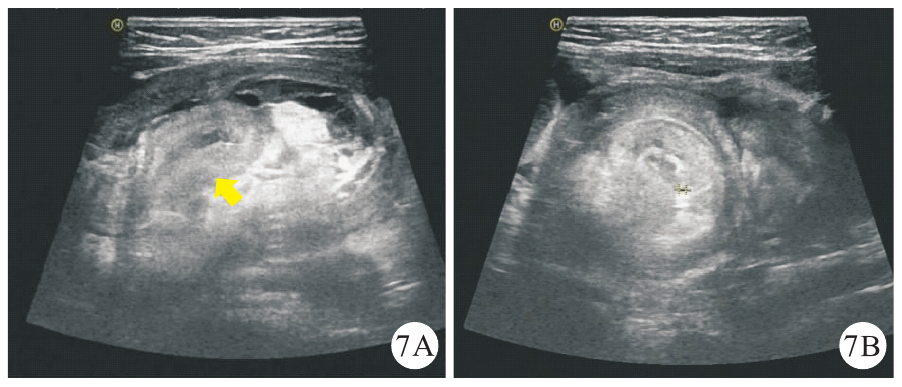

图7 本研究1例无PLP误诊为梅克尔憩室继发肠套叠患儿(男性,8个月龄)的超声声像图[图7A:纵断面套筒内可见水肿增厚的肠壁呈假性偏心厚壁肠袢(黄色箭头所示);图7B:横断面示套筒不伴大于3层的多重靶环征象]注:PLP为病理诱发点